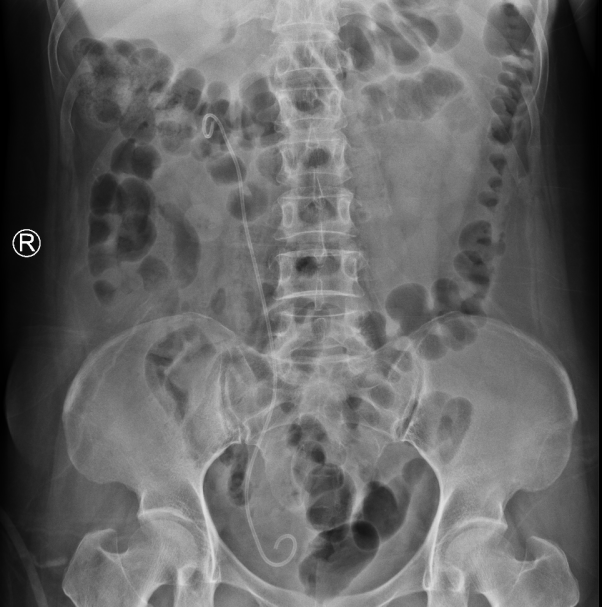

术后第二天吴女士就拔除了导尿管,体温正常,复查血、尿常规提示炎症指标都不高,同时,复查尿路平片发现结石清石率达到了100%,困扰了她许久的问题终于得到了解决。

术前术后尿路平片对比